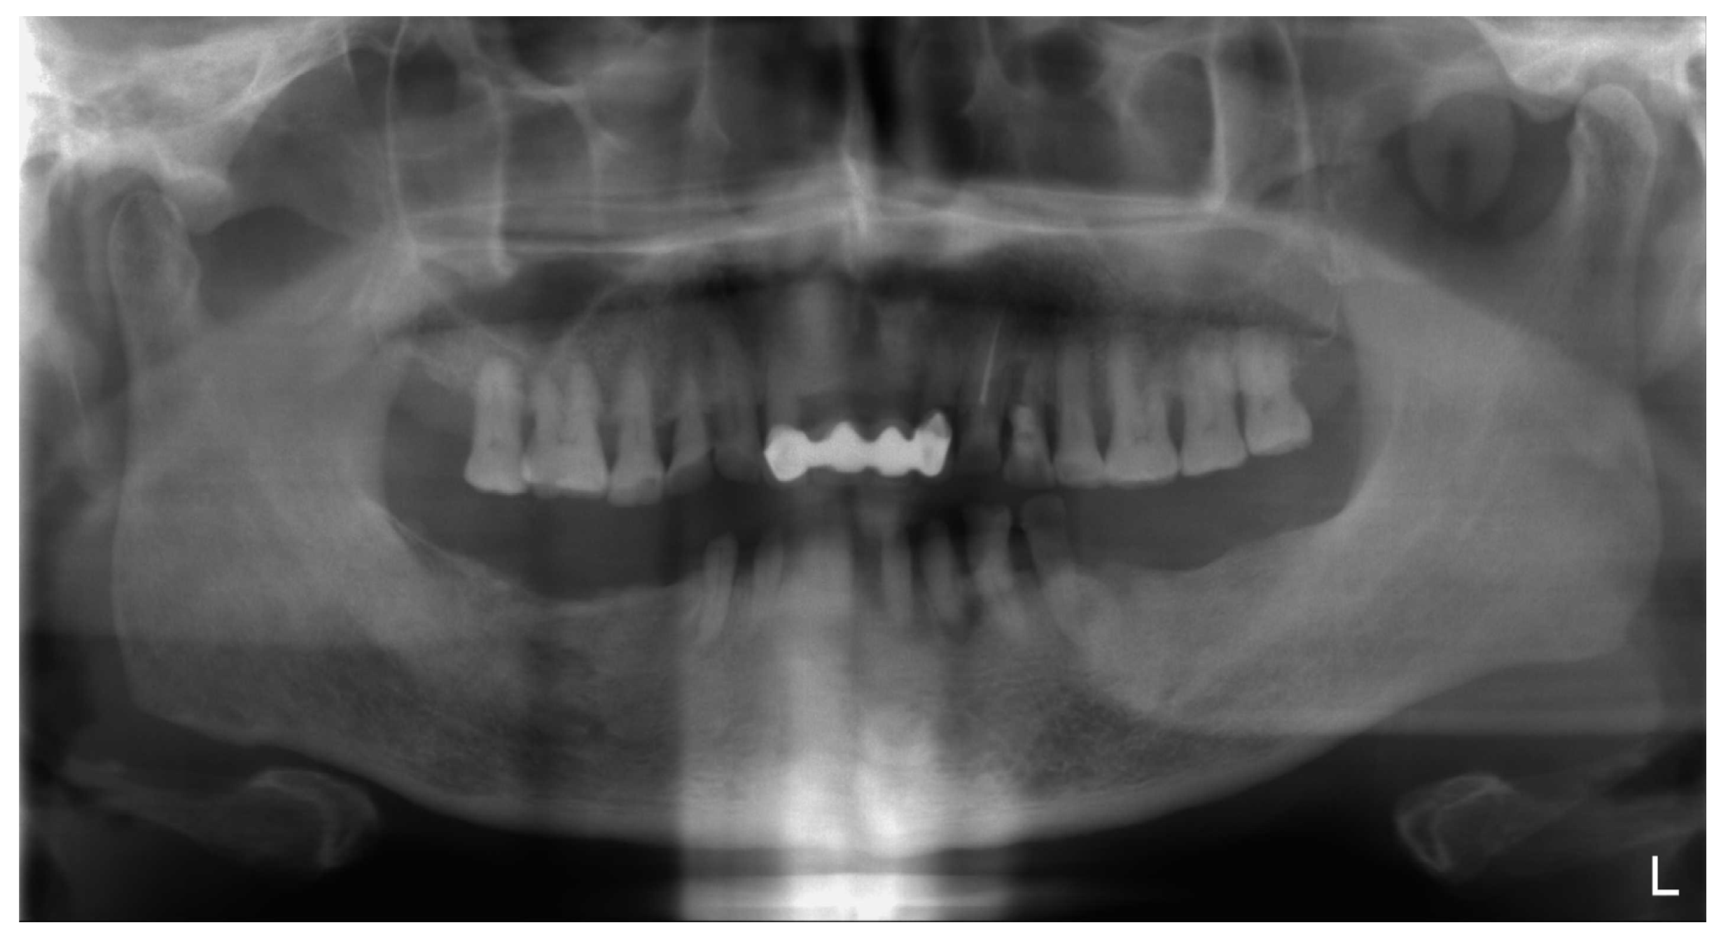

2. Case Description